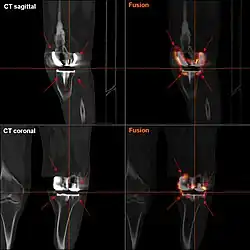

Aflojamiento

El aflojamiento de la prótesis puede estar indicado en la radiografía por espacios radiotransparentes delgados alrededor del implante, o más obviamente por el desplazamiento del implante.[48]

Si bien es relativamente rara, la infección periprotésica sigue siendo una de las complicaciones más desafiantes de la artroplastia articular. Una historia clínica y un examen físico detallados siguen siendo la herramienta más confiable para reconocer una posible infección periprotésica. En algunos casos, pueden estar presentes los signos clásicos de fiebre, escalofríos, dolor en las articulaciones y drenaje de los senos nasales, y los estudios de diagnóstico simplemente se realizan para confirmar el diagnóstico. Sin embargo, en realidad, la mayoría de los pacientes no presentan esos signos clínicos y, de hecho, la presentación clínica puede superponerse con otras complicaciones como el aflojamiento aséptico y el dolor. En esos casos, las pruebas de diagnóstico pueden ser útiles para confirmar o excluir la infección.